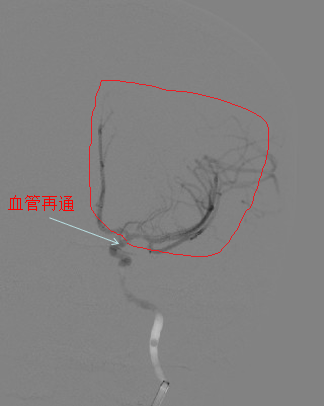

取栓后患者血管再通

刘忠锦副院长带领神经介入小组迅速到达导管室,20分钟后诊断造影确认患者为左侧颈内动脉末端闭塞,47分钟后患者血管内栓子取出,血管再通,前向血流mTICI3级。在神经内科、急诊医学科,导管室和麻醉科通力合作下,手术顺利完成,病人术后复查头CT后送往重症监护室,病情平稳后转回神经内科五病区病房。术后一周,患者脑部功能完全恢复。